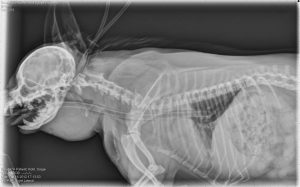

They then, along with Rachel Moon, DVM, DACVR, assistant clinical professor of radiology in the Department of Clinical Sciences at Auburn University's College of Veterinary Medicine, and Scott Bishop, curator of academic and public programs at the museum, entered the classroom to discuss their findings and interpretations. At the end of the session, students applied their newly developed skill set to examine radiographs and other diagnostic images.

According to Dr. Moon, radiology is an integrated process between the art and the science of discovery and the answer is not always apparent, which is why it is important that students can first describe what they are seeing before jumping to possible answers.

"These skills can be used broadly in a number of physical diagnosis situations for veterinarians, including dermatology and ophthalmology," said Dr. Moon. "Their observations and interpretations of the paintings, once they examine them, is exactly the same process that they need to go through when they look at a radiograph."